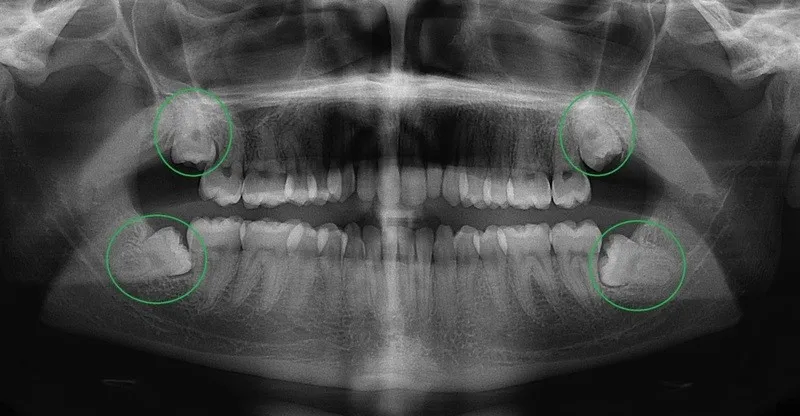

- X-quang giúp bác sĩ phát hiện tình trạng răng khôn mọc lệch, mọc ngang hoặc mọc sai hướng

Kỹ thuật chụp X quang răng khôn vòng quanh mang đến một cái nhìn tổng thể hơn. Đặc biệt về tình trạng răng khôn ở cả hàm trên và hàm dưới. Phương pháp này có sự khác biệt so với chụp X-quang 1 răng khi không cần đưa phim vào bên trong khoang miệng. Thay vào đó, người chụp chỉ cần ngồi yên, và máy X-quang sẽ xoay xung quanh đầu người bệnh. Nhờ vậy, kỹ thuật này không chỉ giúp phát hiện các bệnh lý liên quan đến răng khôn. Nó còn mở rộng khả năng phát hiện các vấn đề về răng miệng.

Chụp X-quang toàn cảnh răng cung cấp một cái nhìn tổng thể nhất về toàn bộ hệ thống răng miệng. Trong đó bao gồm cả răng khôn, hàm răng, xoang vùng mũi và khớp thái dương. Phương pháp này giúp bác sĩ chẩn đoán chính xác các tình trạng. Ví dụ như sâu răng, u nang, răng mọc lệch, hoặc răng ngầm. Việc có được cái nhìn toàn diện này sẽ giúp đưa ra các phương pháp điều trị hiệu quả. Đồng thời đưa ra phù hợp với từng trường hợp cụ thể. Từ đó hạn chế các rủi ro phát sinh trong quá trình điều trị.